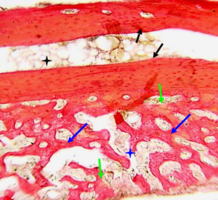

В толще соединительной ткани определяется интенсивное костеобразование – видны тонкие вновь образованные балки молодой костной ткани, окрашенные более интенсивно, чем интактная кость.

В них определяется резко повышенная клеточность - число клеток (остеобластов) на единицу площади по сравнению с прилежащей зрелой костной тканью нижней челюсти, что подтверждает интенсивность клеточного размножения и пролиферации.

Идет активное новообразование капилляров микроциркуляторного русла, обеспечивающее интенсивное кровоснабжение регенерата (рис. 4).

Рис. 4. Нижняя челюсть кролика через 14 суток после остеопластики слева, смесь лиофилизированной аллоспонгиозы и ГАП 1:1.

Синими стрелками обозначены тонкие новообразованные костные балки, содержащие множество активных остеобластов, указанных черными стрелками.

Зелеными стрелками показаны вновь образованные тонкостенные капилляры.

Окраска - пикрофуксин по ван Гизон, х400.